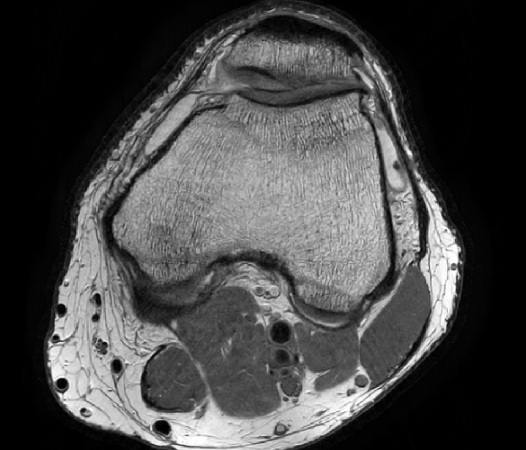

In the example below, only one fifth of the required MR radiofrequency signals is recorded. This results in a five times faster acquisition, with a subsampled k-space (top left) and inherent image artifacts after standard reconstruction (top right).

Basic compressed sensing principle

The Compressed SENSE reconstruction then uses iterative, knowledge-based algorithms to fill in the empty lines in k-space (bottom left). This removes the artifacts while keeping the final image fully consistent with the acquired data (bottom right). *Compared to Philips MR exams without Compressed SENSE